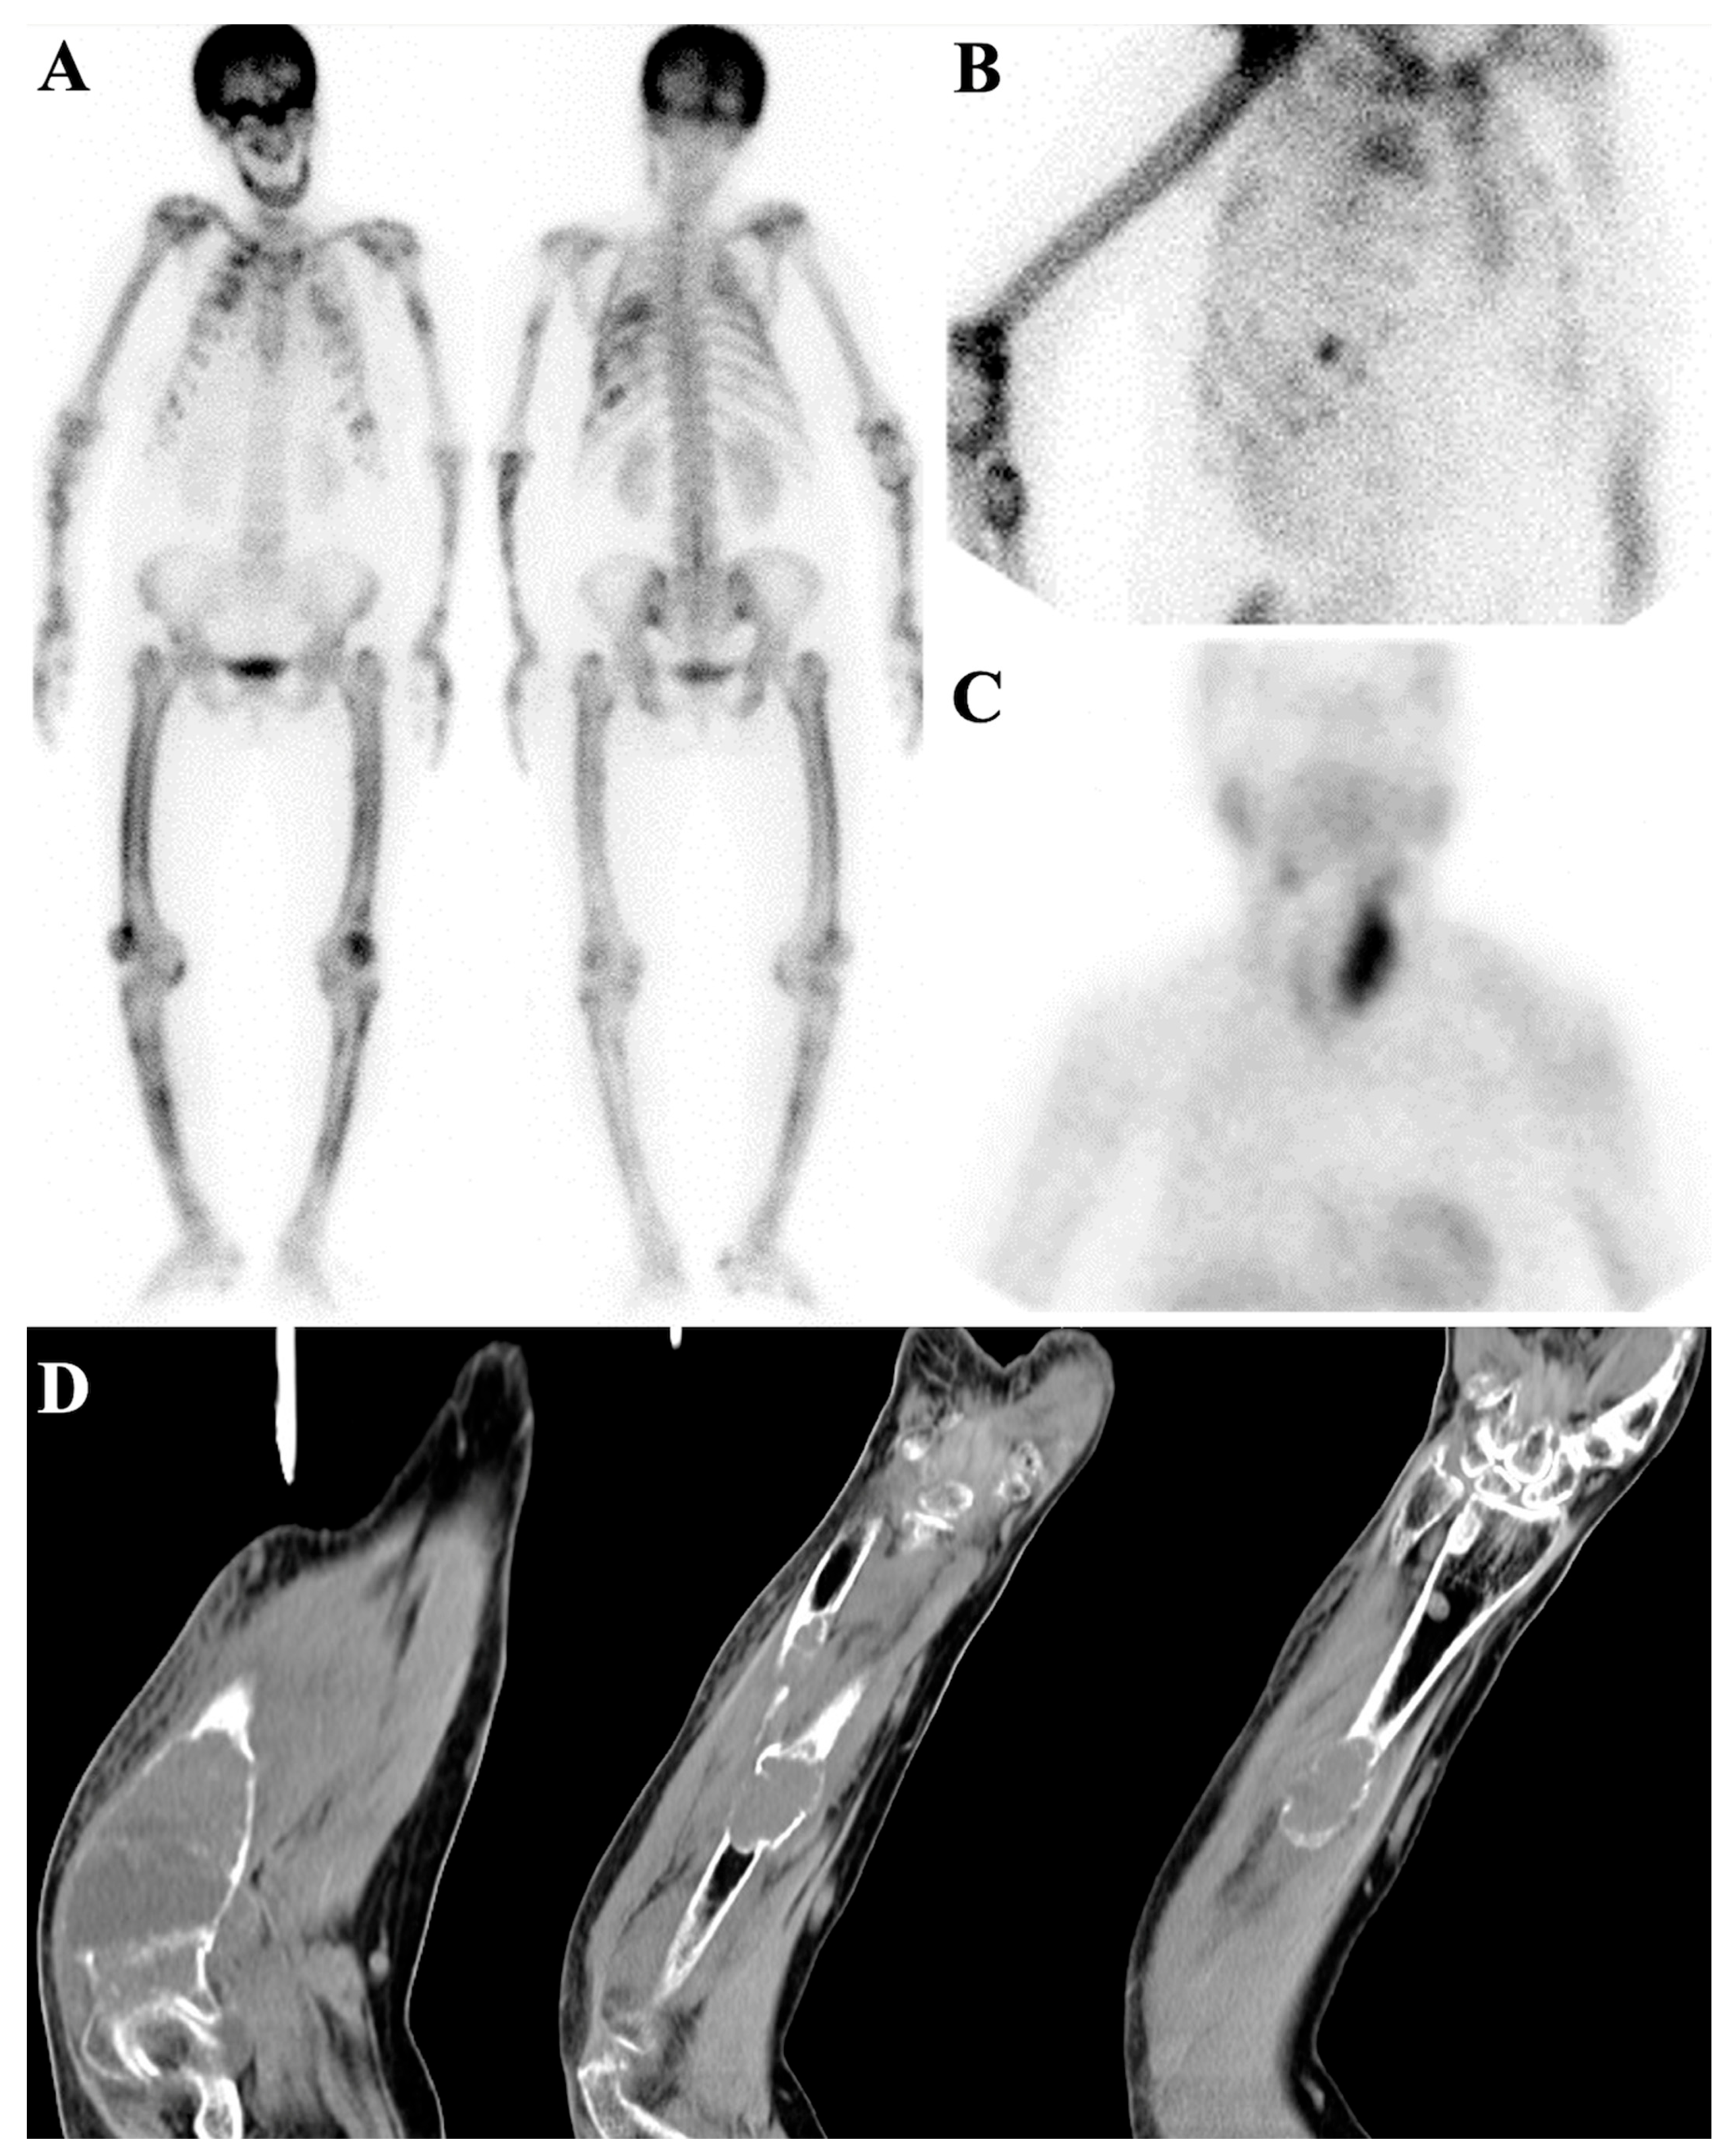

7.2. Metabolic Superscan

7.3. Distinguishing Metabolic Superscan from Metastatic Superscan